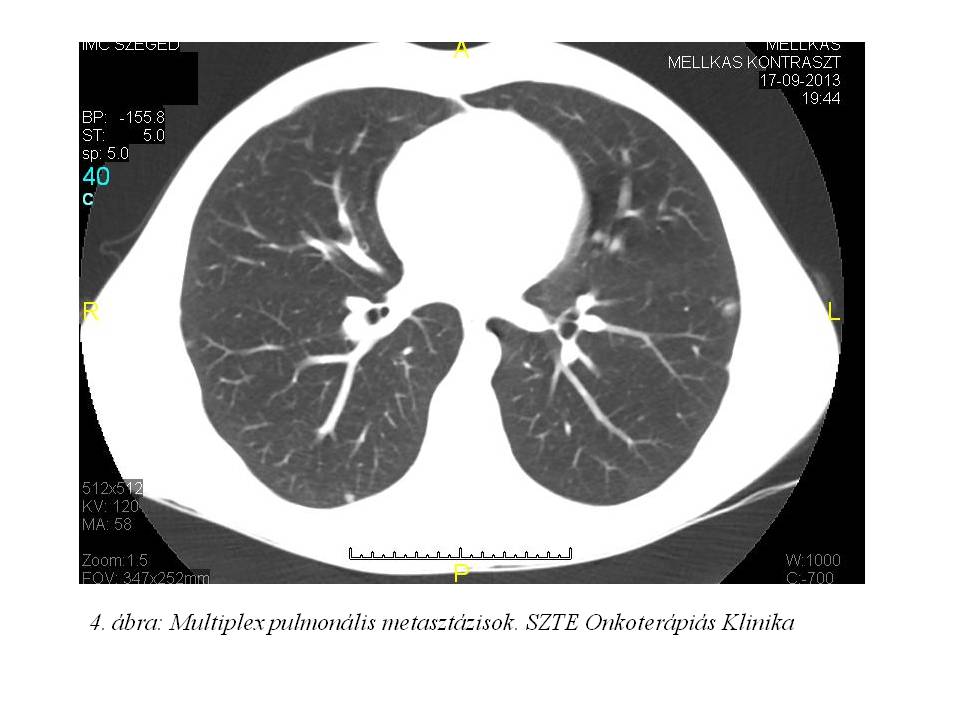

dolt. Júliusra a fájdalom fokozatosan erősödött, RTG vizsgálat (1. ábra) készült, mely traumás eltérést nem írt le, lokális Diprophos-Diclac terápia indult. Fájdalma nem mérséklődött, ellenben folyamatos dagadás és térdhajlati terime növekedést észlelt, MRI (2. ábra, 3. ábra) készült, mely alapján sürgős biopsia történt. A tibia biopsia szövettana desmoplastikus kis kereksejtes tumort (DSRCT) véleményezett, habár a tumor lokalizációja extrém ritka. A DSRCT agresszív, malignus tumor, kifejezetten rossz prognózissal (median túlélés: 17-25 hónap). Általában a primer tumor a hasüregben alakul ki, peritonealis terjedés az elsődleges, majd limfatikus és hematogén áttétképződés, különösen a májba. Staging vizsgálatai során disszeminált csontérintettséget, limfatikus és pulmonalis metasztázisokat írtak le (4. ábra, 5. ábra). A szakirodalom áttekintését követően 2013.10.14-én VIDE (Vincristine, Ifosfamide, Doxorubicin, Etoposide) kemoterápiás, ill. a disszeminált csontérintettség miatt zoledronsav kezelést kezdtünk. A felvételkor csak segédeszközzel, és igen nehezen mozgott, idejének több mint 50%-át ágyban töltötte, állandó medencefenék, keresztcsonti zsibbadásról, vizelet- és széklet-ürítési panaszokat említett.